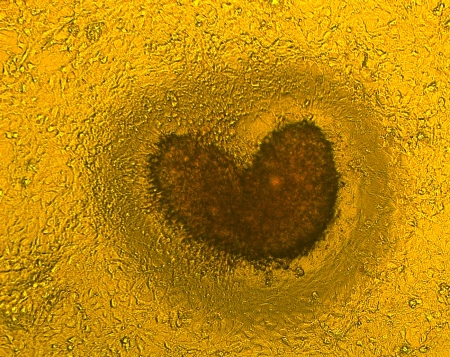

১। করোনা লাভ

ছবি তে দেখা যাচ্ছে করোনা ভাইরাস (যার সাথে গ্লো করার প্রোটিন লাগানো আছে)। এটা বিড়াল এর করোনা ভাইরাস। ভাইরাস কে যখন বিড়াল থেকে নেওয়া কোষ এর কালচার মাঝে দেওয়া হল ১২ ঘন্টার মাঝে বিড়াল এর কোষ কে চার দিক 'এটাক' করে কোষে প্রবেশ করছে। এই প্রসেস এর দ্বারা এক কোষ থে কে আরেক কোষে ইনফেকশান করে সে 'প্লাক (Plaque)' তৈরী করে.. প্লাক এর এই শেইপ টা দেখে মনে হচ্ছে ছবির নাম 'করোনা লাভ' হওয়াই উচিত।

২। করোনা লাভ-২

এই ছবিটা ১ং ছবিই কিন্তু এখানে বিড়াল এর কোষের কালচার এর সাথে করোনা ভাইরাস একসাথে দেখা যাচ্ছে। ১ং ছবিটা ফ্লোরেসেন্স মাইক্রোস্কপে তোলা। ২ নং টা জাস্ট ব্রাইট ফিল্ড ছবি।